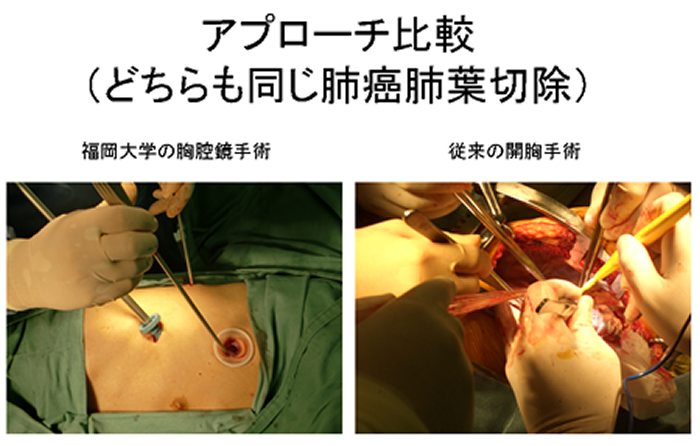

選ぶなら 気道・肺の腫瘍 (呼吸器病New Approach 9) | 飛田 渉 |本 | 通販 医学一般